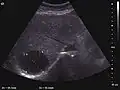

Hydatid liver cyst. Diagnostic criteria are the presence of membranes and sediment inside.

The ultrasound appearance is a well defined lesion, with very thin, almost unapparent walls, without circulatory signal at Doppler or CEUS investigation. The content is transonic suggesting fluid composition. The presence of membranes, abundant sediment or cysts inside is suggestive for parasitic, hydatid nature. Posterior from the lesion the acoustic enhancement phenomenon is seen, which strengthens the suspicion of fluid mass. They typically displace normal liver vessels but no vascular or biliary invasion occurs.